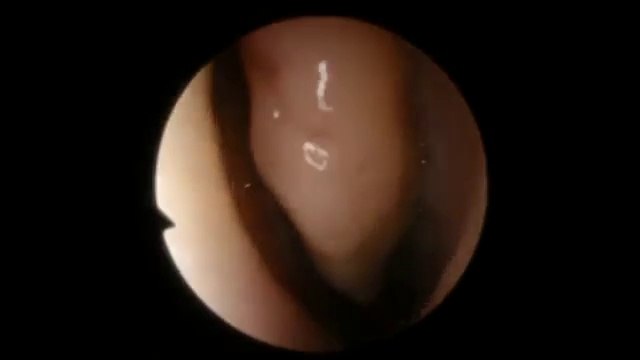

Chronic Sinusitis and Acute Sinusitis, Sinisitus

sinusinfectiondiscovery.com Get 20 FREE Sinusitis Symptoms VIDEOS. Free info on sinus treatment, sinus infection, sinus pain, sinus headache, sinus congestion and Post Nasal Drip. FREE